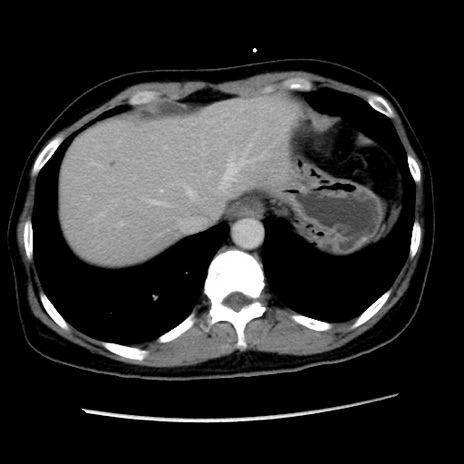

冠状断像

【症例】 50歳代女性

【主訴】 腹痛

【現病歴】前日生レバーを食べた。今朝に排便あり。 昼前に突然発症の腹痛を生じ、当院救急外来を受診した。

【既往歴】 子宮筋腫にてで子宮全摘後

【身体所見】 意識清明、腹部:平坦、軟、下腹部やや左を中心に圧痛・反跳痛あり、筋性防御あり

【データ】WBC 7800、CRP 0.07